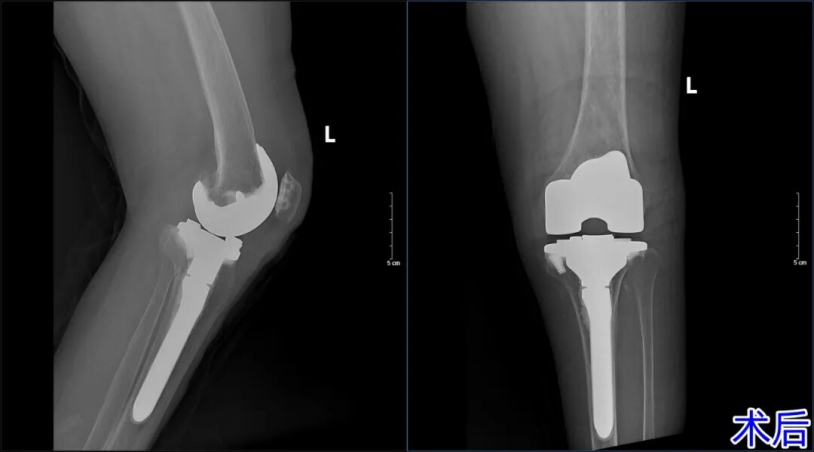

手术台上,杨学良主任凭借二十余年的深厚积淀,精准清除了病变组织,成功矫正了畸形并稳固植入了人工假体;病房内,护理团队贯彻加速康复理念,24小时无缝隙守护,将伤口护理、疼痛管理与康复训练环环相扣。

如今,王奶奶的左膝不仅能平稳承重,更能自主屈伸,饮食与睡眠也重归正轨。“真没想到,这把年纪还能走得这么稳当!”老人的由衷感慨,是对骨二科全体医护人员最高的褒奖。